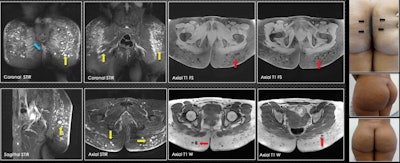

MRI provides the most information to the radiologist and should be done on all patients, they stated. "It can warn the surgeon about the level of tissue compromise. It shows the affected planes and the approximate amount of biopolymers injected. It demonstrates their areas in the case of material migration."

Additionally, MRI presents the biopolymer in encapsulated form (rounded-oval or elongated vesicles). The round and elongated vesicles can be seen affecting the subcutaneous cellular tissue, so the location is superficial, while the elongated ones are found on deep planes, infiltrating the gluteal fibers.

"Regarding the most frequent areas of migration, we have found that soft tissues of the lumbosacral region are the most frequent, followed by the bilateral ischiorectal region, female external genitalia, and lower limbs," they noted.

A few weeks after placing the biopolymers, liquid forms can be seen that simulate seromas without vesicles. After six to 12 months, seromas and vesicles coexist. After more than 18 months, only vesicles containing the biopolymer material are found. In many patients, there is migration from deep to superficial planes, which, due to their shape and distribution, suggests that lymphatic drainage has occurred.

The length of time that patients carry the biopolymer in the buttocks plays an important role in the way the material will be presented in tissues, the authors wrote.